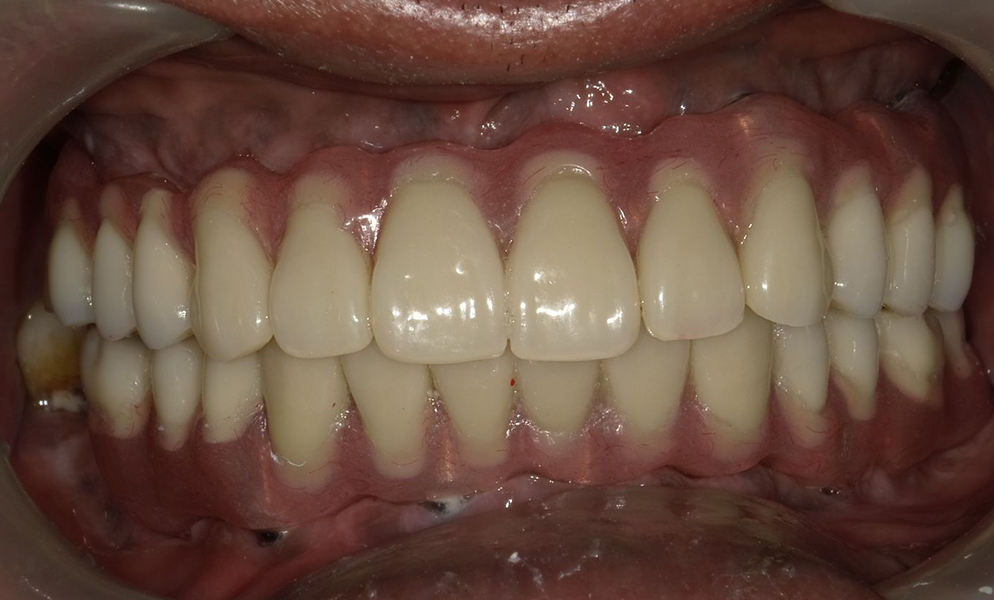

![]() |

| Full-mouth reconstruction with short dental implant (Bicon, USA)-supported prosthesis | |